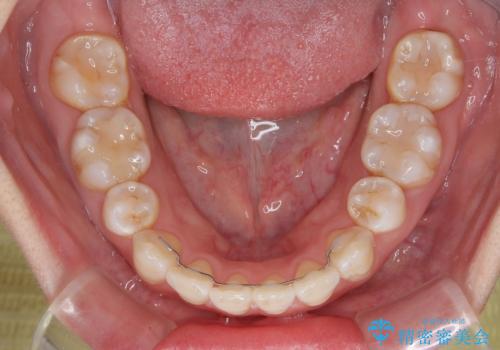

- 上下前歯の後戻りを気にして来院された患者様です。

インビザラインでの治療を希望されていて、デコボコの程度が中等度であり、安価なパッケージにて対応可能と判断されたため、インビザライン・モデレートを用いて矯正治療を行うこととしました。